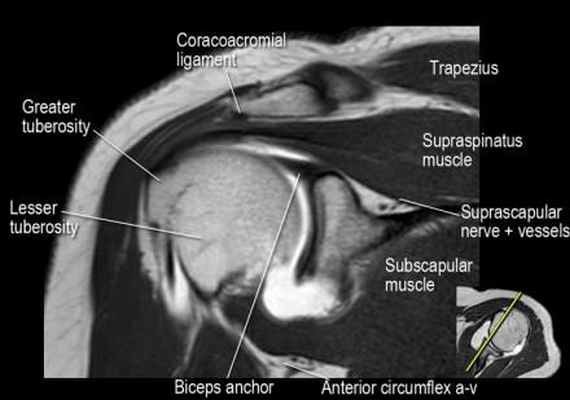

Нормальная корональная анатомия плечевого сустава и контрольный список

- обратите внимание на клюво-ключичную связку (coracoclavicular ligament) и короткую головку двуглавой мышцы (short head of the biceps).

- обратите внимание на клювоакромиальную связку (coracoacromial ligament).

- -

- обратите внимание на надлопаточный нерв и сосуды (suprascapular nerve and vessels)

- поищите импинджмент надостной мышцы за счет остеофитов в акромиально ключичном суставе или из-за утолщения клювовидноакромиальной связки.

- изучите верхний комплекс двуглавой мышцы и суставной губы, поищите подгубный карман илм SLAP-повреждение

- поищите скопление жидкости в подакромиальной сумке и повреждение сухожидия надостной мышцы

- поищите частичный разрыв сухожилия надостной мышцы в месте его прикрепления в виде кольцевидного повышения сигнала

- изучите область прикрепления нижней плече-лопаточной связки. Изучите нижний комплекс суставной губы и связок. Поищите HAGL-повреждение (humeral avulsion of the glenohumeral ligament).

- поищите повреждение сухожилия подостной мышцы

- обратите внимание на небольшое повреждение Хилл-Сакса